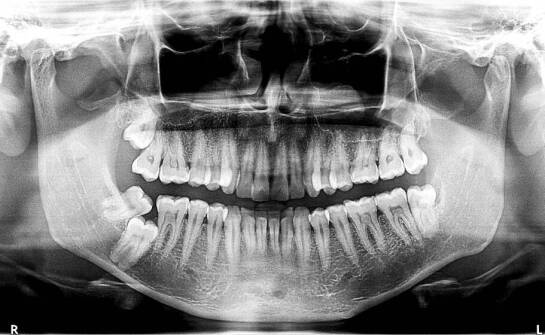

Rola rentgena w planowaniu leczenia stomatologicznego - co warto wiedzieć?

Rentgen zębów odgrywa kluczową rolę w diagnostyce stomatologicznej, umożliwiając lekarzom dokładne zrozumienie stanu zdrowia pacjentów. Dzięki nowoczesnym technologiom rentgenowskim, takim jak usługi rentgenowskie zębów w Poznaniu i okolicach, podejście do diagnostyki ulega zmianie, przynosząc korzy